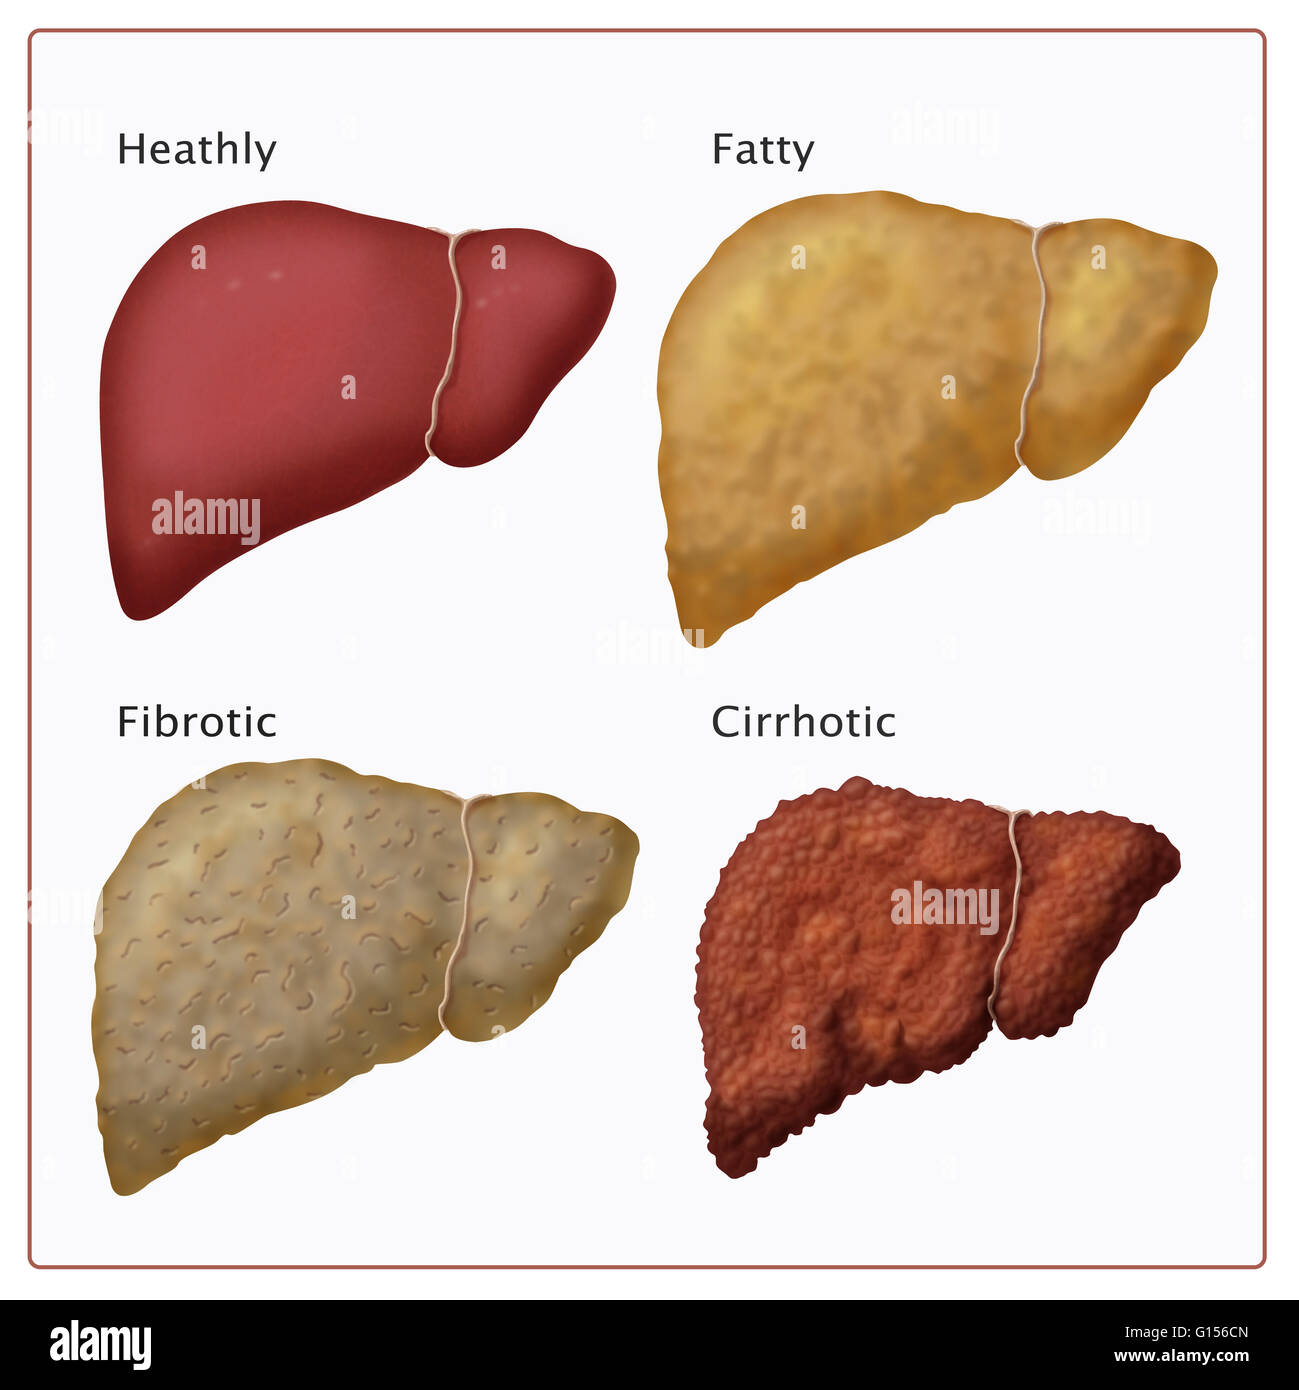

Stages of Liver Damage, Illustration – Stock Image – C027/6479 …

Stages of liver damage. Starting from a healthy liver (top left Stock …